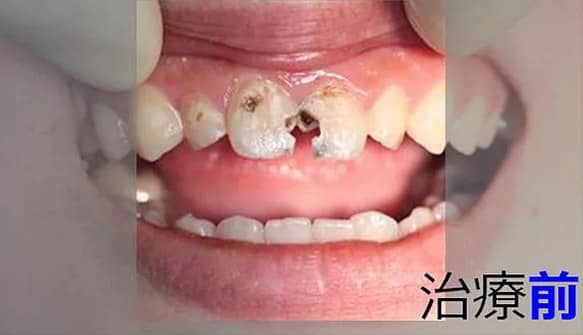

3虫歯/被せもの【虫歯の治療例1】

治療前

治療後

​患者様の希望で被せずに詰め物だけで治しました。